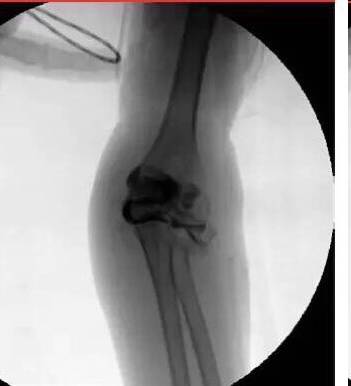

难推动倒斜下的桡骨颈,闭合复位失败,2.0 克氏针扁头经皮撬拨骨折断端,克氏针钝头复位骨折。

取出复克氏针,已经比较稳定,但侧片看见桡骨近端仍有轻微向后、外移位趋势,存在潜在不稳定。

1.5 克氏针固定,避免向后外移位趋势(术后正、侧位X线片及置针的肘部外观)